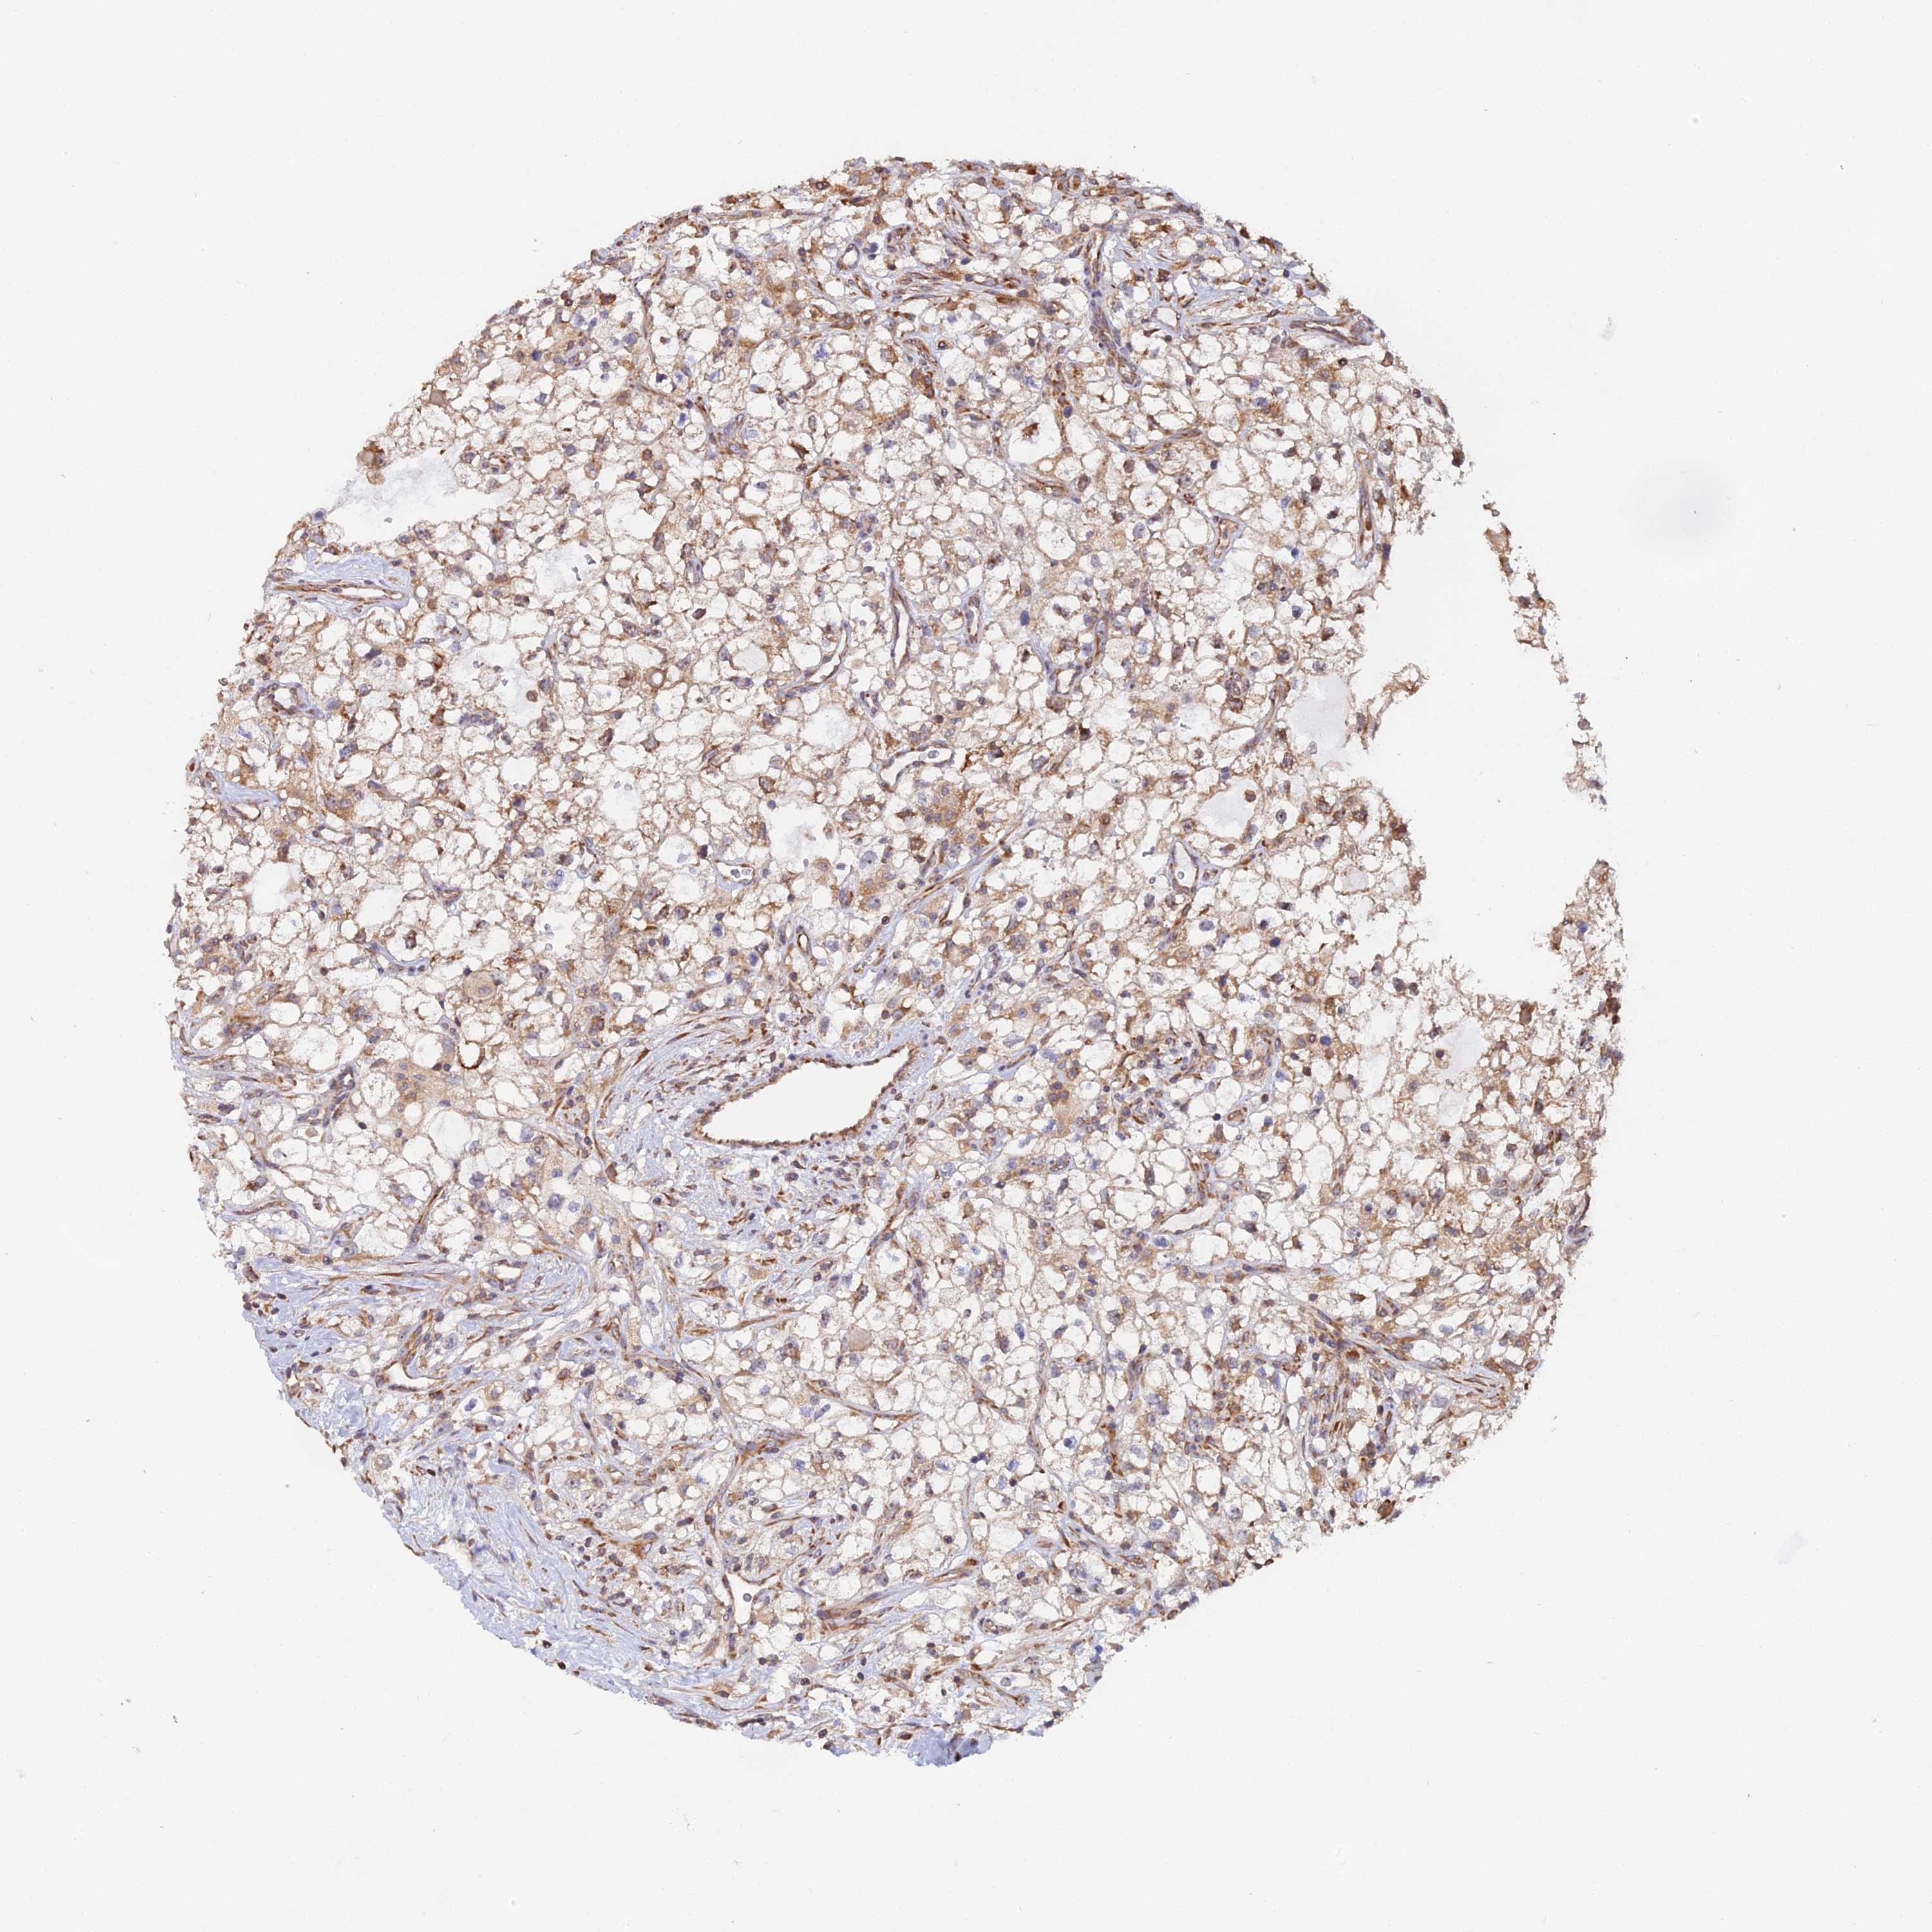

KIDNEY RENAL CLEAR CELL CARCINOMA (VALIDATION) - Interactive survival scatter ploti

The Survival Scatter plot shows the clinical status (i.e. dead or alive) for all individuals in the patient cohort, based on the same data that underlies the corresponding Kaplan-Meier plots. Patients that are alive at last time for follow-up are shown in blue and patients who have died during the study are shown in red.

The x-axis shows the expression levels (FPKM) of the investigated gene in the tumor tissue at the time of diagnosis. The y-axis shows the follow-up time after diagnosis (years). Both axes are complimented with kernel density curves demonstrating the data density over the axes. The top density plot shows the expression levels (FPKM) distribution among dead (red) and alive patients (blue). The right density plot shows the data density of the survived years of dead patients with high and low expression levels respectively, stratified using the cutoff indicated by the vertical dashed line through the Survival Scatter plot. This cutoff is automatically defined based on the FPKM cutoff that minimizes the p-score. The cutoff can be changed by dragging the vertical line or by entering a cutoff value in the square labeled "Current cut-off".

Under the Survival Scatter plot the p-score landscape (black curve; left axis) is shown together with dead median separation (red curve; right axis). Dead median separation is the difference in median mRNA expression between patients who have died with high and low expression, respectively. It is calculated as follows: median FPKM expression of dead patients with high expression - median FPKM expression of dead patients with low expression. This is intended to aid the user in visually exploring custom cutoffs and the associated p-scores and dead median separation.

Individual patient data is displayed and can be filtered by clicking on one or more of the category buttons on the top of the page. Categories describing expression level and patient information include: high, low, alive, dead, female, male and tumor stages. The scale of the x-axis can be toggled between linear and log-scale by clicking on the "x log" button. Mouse-over function shows TCGA ID, patient information and mRNA expression (FPKM) for each patient.

& Survival analysisi

Kaplan-Meier plots summarize results from analysis of correlation between mRNA expression level and patient survival. Patients were divided based on level of expression into one of the two groups "low" (under cut off) or "high" (over cut off). X-axis shows time for survival (years) and y-axis shows the probability of survival, where 1.0 corresponds to 100 percent.

RPL26 is not prognostic in Kidney Renal Clear Cell Carcinoma (validation)

Best expression cut offi

Based on the FPKM value of each gene, patients were classified into two groups and association between prognosis (survival) and gene expression (FPKM) was examined. The best expression cut-off refers the FPKM value that yields maximal difference with regard to survival between the two groups at the lowest log-rank P-value. Best expression cut-off was selected based on survival analysis .

When clicking on this number, the vertical dashed line indicating cut-off, the interactive survival plot, and the Kaplan-Meier curve will be adjusted to show results based on the best expression cut-off.

: 2501.78

Average pTPM 2601.9

Number of samples 100